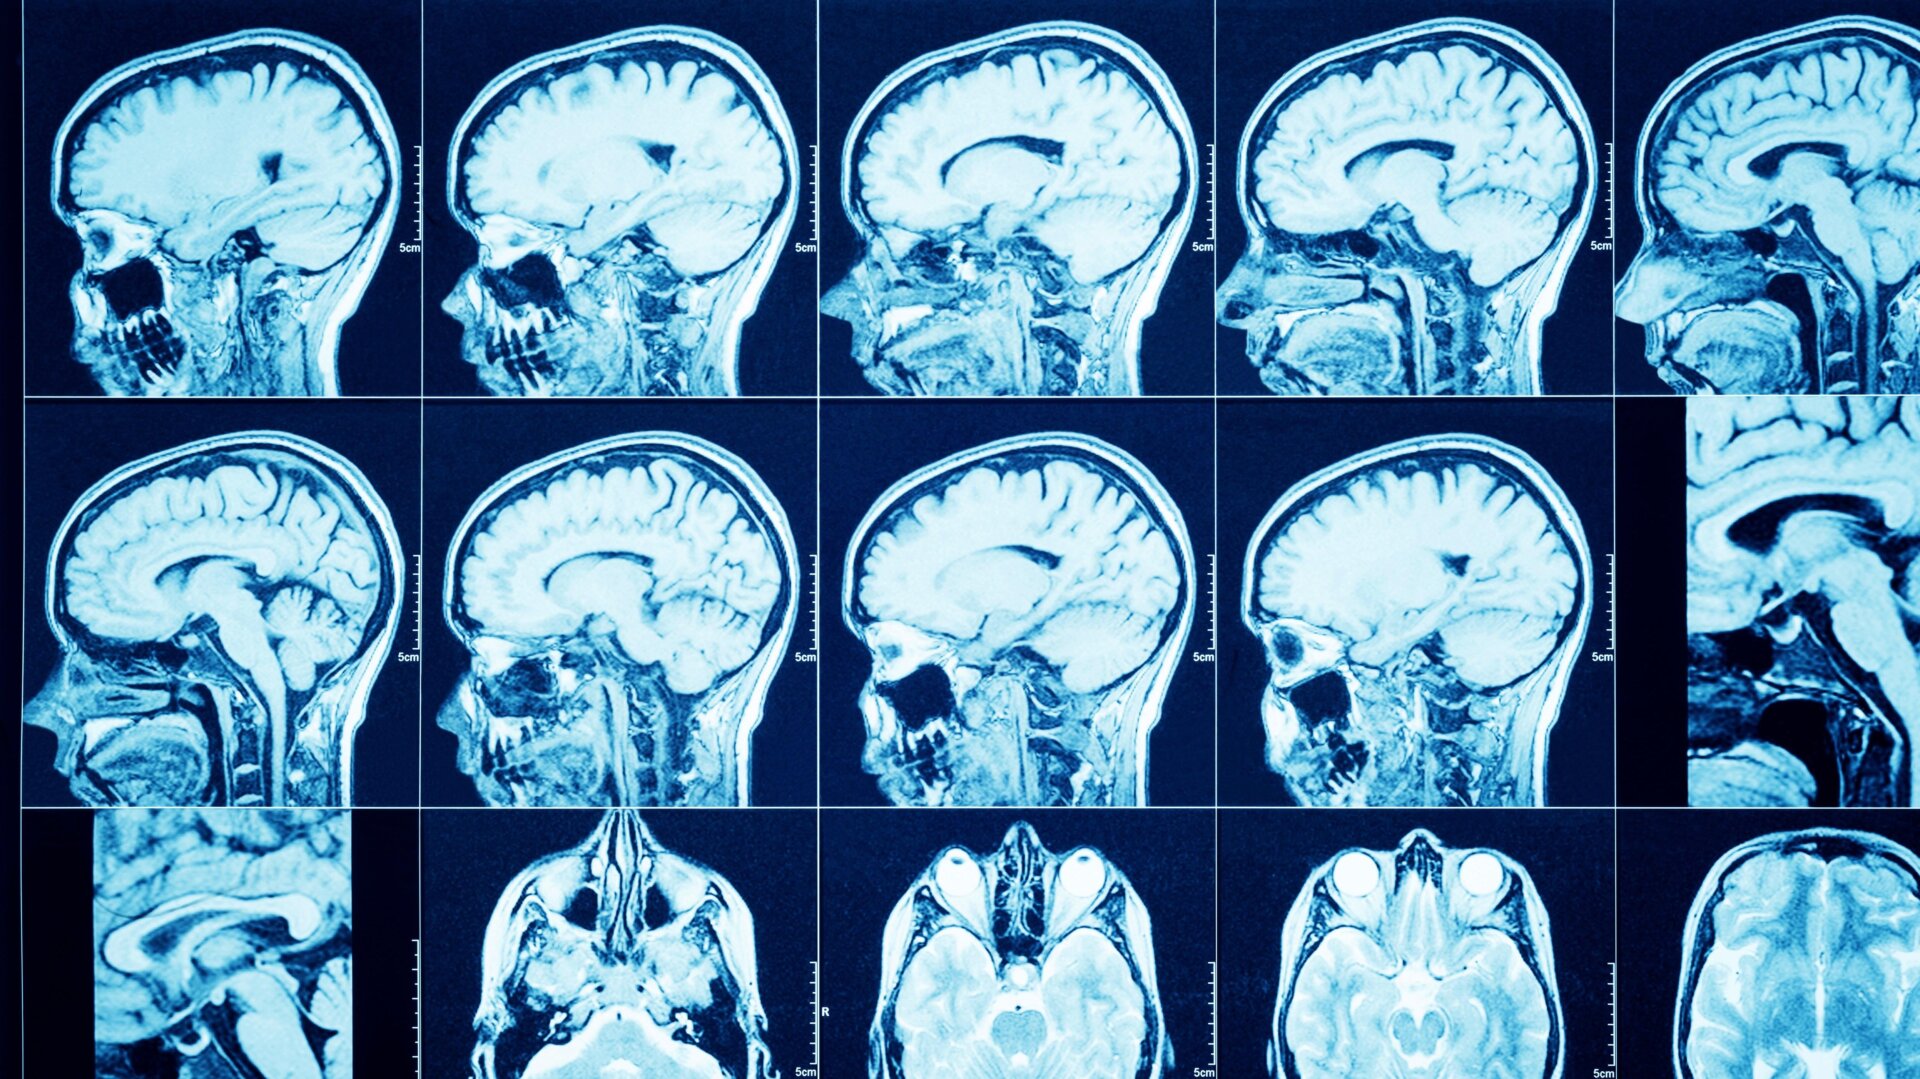

El extraño caso fue reportado a principios de este mes por funcionarios de salud locales en Sajalín, una isla remota frente a la región del Lejano Oriente de Rusia. Los médicos de la mujer supuestamente descubrieron la aguja de 3 centímetros durante una tomografía computarizada no relacionada de su cerebro. Las imágenes de la aguja se pueden visto en la página de Telegram del departamento de salud.